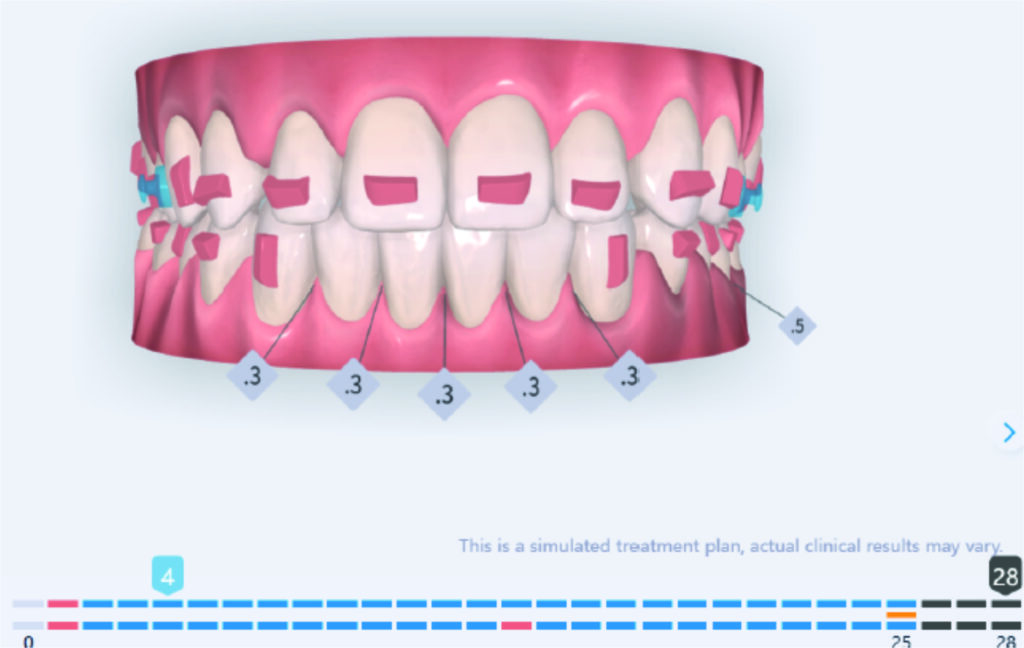

IPR of the lower anterior segment was performed to address Bolton discrepancy.

The case initially presented as a moderate Class II on the right and a Class II tendency on the left, with tapered dental arches and an anterior open bite extending to tooth 26 in segment II.

In segment I, the open bite reached up to the first premolar.

A 1.5 mm deviation of the upper dental midline to the patient’s left was noted, along with a slight mandibular midline shift to the right, likely due to asymmetrical mandibular growth observed in the facial structure. Severe mesial rotations of teeth 16 and 26 were evident in the initial records. As derotation of 16, 26, 17, and 27 progressed up to aligner 16, the premolars in segments I and II moved distally, resulting in a bilateral Class I relationship, as intended in the initial treatment plan.

No sequential distalization for Class II tendency correction was performed due to skeletal anchorage. Lingual attachments were used to improve aligner grip and control tooth movement, as small, angulated lower incisors are difficult to move due to limited anatomy.